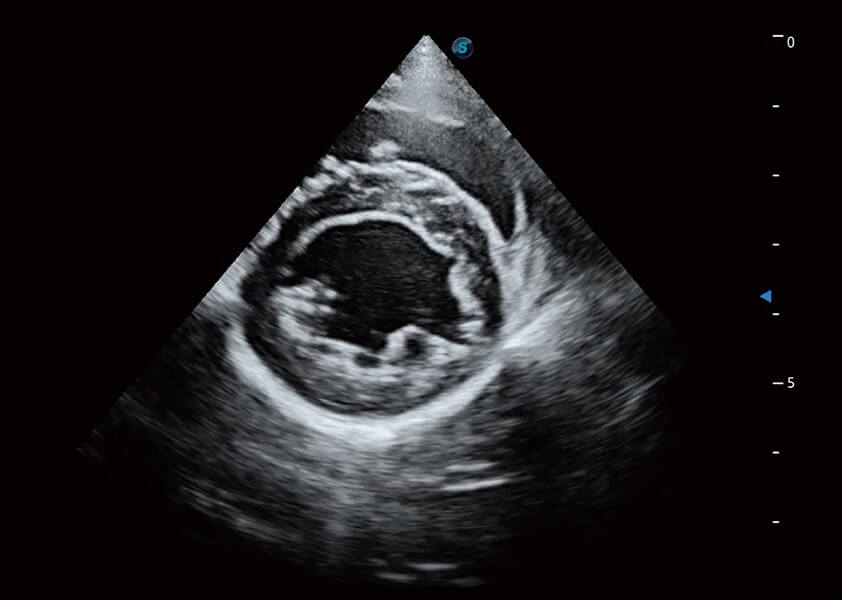

优异的基础图像

(犬)乳头肌短轴

(猫)二尖瓣M型